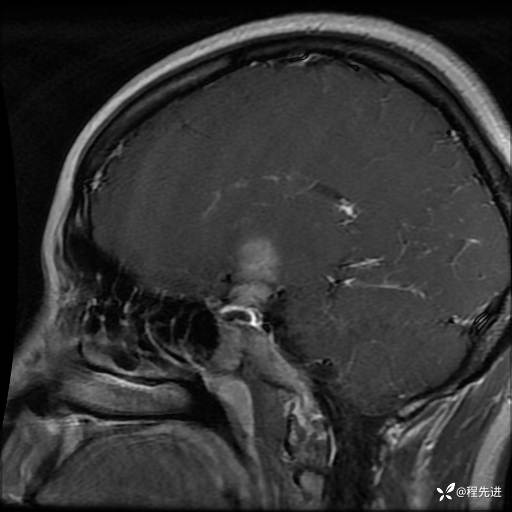

MRI平扫+增强:

T1+C: